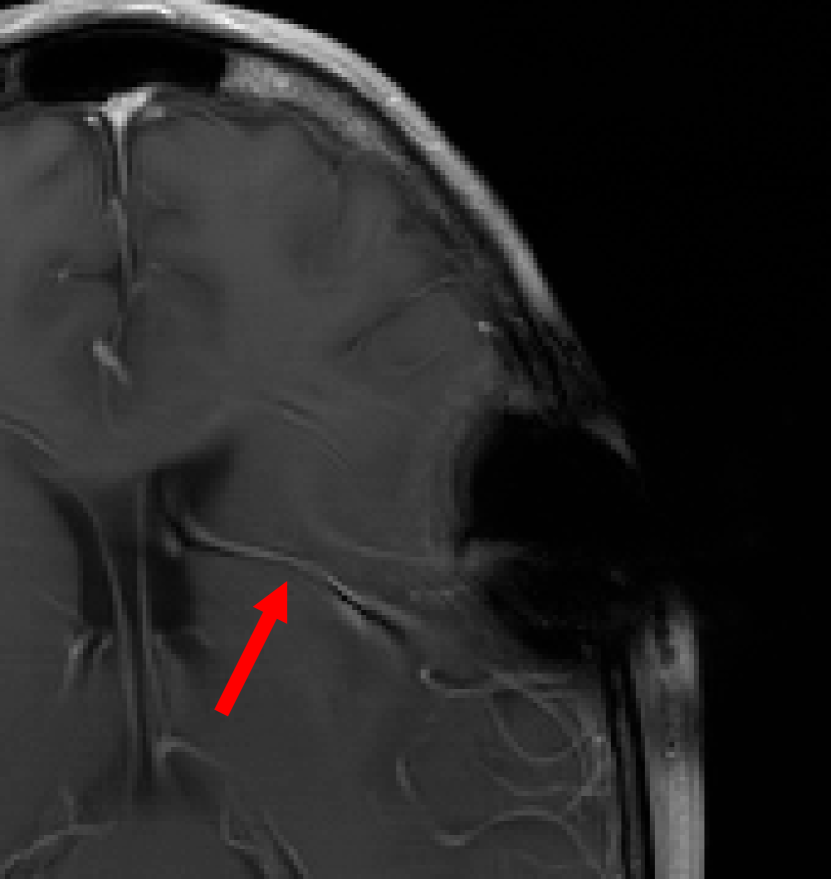

This result implies that random noise can also produce undesirable effects. In Fig. 3 we show several examples of this effect. For the first DL method, mean zero Gaussian noise causes the NN reconstruction map to hallucinate, by artificially removing an image feature (indicated by the red arrow). In the second case, certain image independent, small mean Gaussian noise causes severe instabilities in the recovered image. Notice that the noise causes the second DL method to exhibit completely nonphysical artefacts, which could be easily identified by a practitioner as a failure mode. Yet for the first method it creates seemingly realistic artefacts (hallucinations). Such pernicious artefacts may be impossible to detect.

Hallucinations with zero-mean Gaussian noise Instabilities w.r.t. to Gaussian noise with image independent mean

Noisy image: Noisy image:

|x+v|𝑥𝑣|x+v| |x+v|𝑥𝑣|x+v|

(full size) (cropped)

Refer to caption Refer to caption

DeepMRI-net: DeepMRI-net:

|Ψ(A(x+v))|Ψ𝐴𝑥𝑣|\Psi(A(x+v))| |Ψ(Ax)|Ψ𝐴𝑥|\Psi(Ax)|

(cropped) (cropped)

\begin{overpic}[width=433.62pt]{plots/im_noise1_fact_3_rec_worst_100_place_2_crop.png} \put(68.0,42.0){\color[rgb]{1,0,0}\definecolor[named]{pgfstrokecolor}{rgb}{1,0,0}\vector(1,4){6.0}} \end{overpic} Refer to caption

AUTOMAP: AUTOMAP:

Ψ(Ax+e0)Ψ𝐴𝑥subscript𝑒0\Psi(Ax+e_{0}) Ψ(Ax+e1)Ψ𝐴𝑥subscript𝑒1\Psi(Ax+e_{1})

(full size) (full size)

Ψ(Ax+e2)Ψ𝐴𝑥subscript𝑒2\Psi(Ax+e_{2}) Ψ(Ax+e3)Ψ𝐴𝑥subscript𝑒3\Psi(Ax+e_{3})

Figure 3: (Hallucinations and instabilities due to random noise) Two DL methods exhibit hallucinations and instabilities due to random noise. On the left, the DeepMRI-net [66] reconstruction map is unstable to mean-zero Gaussian noise v𝑣v. In this case, the NN hallucinates by removing a key image feature (see the red arrow). On the right, the AUTOMAP [82] reconstruction map is unstable to Gaussian noise. The noise vector e0subscript𝑒0e_{0} is drawn from a zero-mean Gaussian distribution, whereas the mean of the distribution, used to generate e1,e2subscript𝑒1subscript𝑒2e_{1},e_{2} and e3subscript𝑒3e_{3}, is based on three worst-case noise vectors computed for AUTOMAP with respect to a different image. This makes the mean is image independent. As we can see, the instability of the map produces noticeable artefacts. The measurement matrix in these experiments is a subsampled Fourier transform with 33% (left) and 60% (right) subsampling, respectively. See §A for further information.